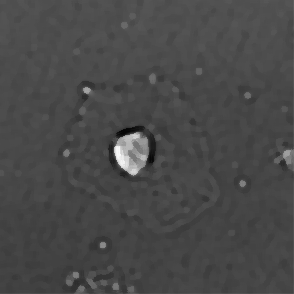

(a) Frame 1. Cell attachment phase

Figure 3: Original images of sequence is example of high dynamics of cell behavior affecting on contrast properties

The Fig.3 is representing couple of frames of sample image sequence with relatively high contrast between foreground and can be segmented with almost 95% accuracy with any method we used. Frame 1 of sample sequence presented at Fig.3(a) contain regions of hyper contrast pixels. In this case such condition does not affect on valid recognition since they are belong to object and present on margins of it and differs well from background. For Frame 2 there is absence of such pixels (Fig.3(b)) and this conditions also makes segmentation possible in relatively inflexible filtering conditions. The Frame 2 has relatively low contrast however it is seen that after filtration applied on image we achieve good difference of core and cell body compared to background as it presented at Fig.4 .